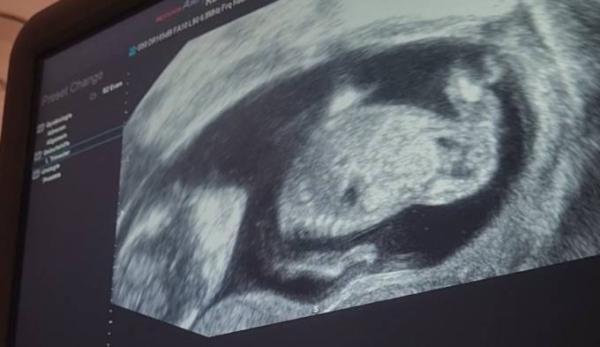

Ich hatte am Montag wieder Termin. Die Ärztin ist sehr zufrieden, es sieht alles so aus wie es aussehen soll Obwohl ich jung und gesund bin, hatte ich doch große Angst, dass im frühen Stadium noch etwas passieren kann. Aber so langsam kann ich die Schwangerschaft einfach nur noch genießen, besonders auch, weil die permanente Übelkeit langsam nachlässt und der Hunger wieder kommt Wir haben eine Tendenz zum Mädchen ich hänge noch ein Bild an, vielleicht sieht die ein oder andere ja auch ein Mädchen? Nächsten Montag wissen wir es dank des Harmony Tests aber zu 100%

Bild zu So fängt das Jahr (trotzdem) gut an :) - Forum für Juli - Mamis

Und hier noch ein Schnappschuss:)

Bild zu